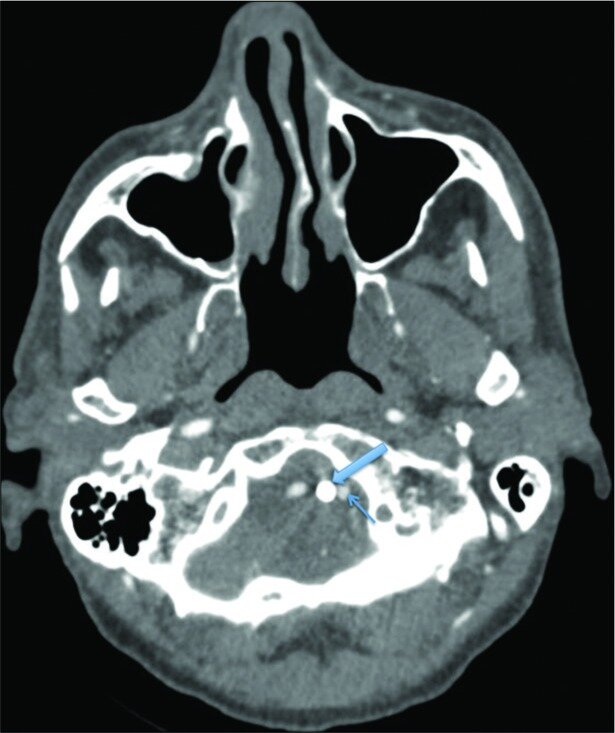

Case description: A 64-year-old neurologically intact patient with a type II odontoid fracture secondary to trauma underwent anterior odontoid screw fixation without any intraoperative complications. He tolerated the procedure well, and postoperative imaging demonstrated near anatomic correction of the fracture with satisfactory placement of the lag screw. Unfortunately, the patient was subsequently lost to follow up and he presented 7 months later for a routine outpatient computed tomography (CT) of the cervical spine, which demonstrated upward migration of the screw into the intracranial cavity abutting the medulla, with CT angiography of the neck also confirming the screw lying between the two vertebral arteries. Magnetic resonance imaging of the cervical spine also demonstrated the odontoid screw lying within close proximity to the ventral cervicomedullary junction, marginating the left vertebral artery. Subsequently, the patient was managed with removal of the odontoid screw and posterior cervical arthrodesis and instrumented fusion.